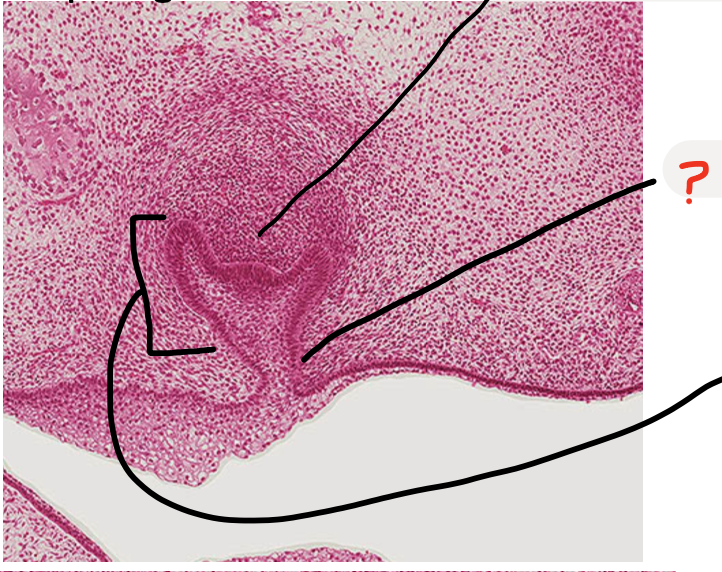

cervical loop

dental follicle

enamel organ

oral epithelium

successional dental lamina

alveolar bone